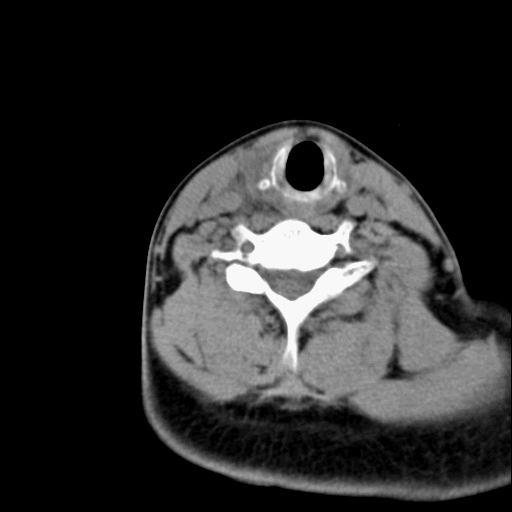

标题: CT23947 右颈部触及00.5x1.5cm质硬长形肿块,疼痛 [打印本页]

标题: CT23947 右颈部触及00.5x1.5cm质硬长形肿块,疼痛

右侧甲状腺腺瘤考虑

甲状腺癌可疑

右侧甲状腺病灶,建议增强或结合b超检查。

右甲状腺占位,建议增强。

甲状腺腺瘤或癌

甲状腺占位  定性有时很难 但无论癌还是腺瘤 还是手术比较好!以下是甲状腺占位的ct鉴别诊断

ct表现:形态不规则的软组织密度肿块,可累及部分或大部分甲状腺组织,密度不均,可坏死、囊变、钙化,增强病灶呈不均匀强化,有局部侵犯或转移时可有颈部淋巴结肿大。

ct表现肿瘤呈稍低密度结节状肿块,边缘光整、锐利病灶均匀强化,少数腺瘤可有钙化。